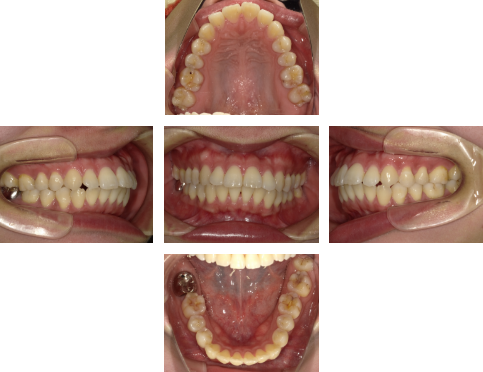

【初診時】

初診時の口腔内写真では、強い叢生(ガタつき)は目立ちません。しかし横から見た写真では、上下の前歯の前方突出が確認できます。

この症例では、歯を後方へ移動させるためのスペースが不足しているため、非抜歯では十分な改善が困難と判断しました。